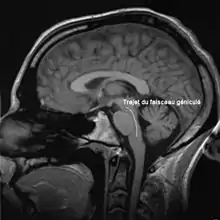

Le faisceau cortico-bulbaire relie le cortex moteur aux noyaux, origines des nerfs crâniens, dans le tronc cérébral. Dans son chemin, il traverse le genou de la capsule interne, ce qui lui vaut le qualificatif de « géniculé ».